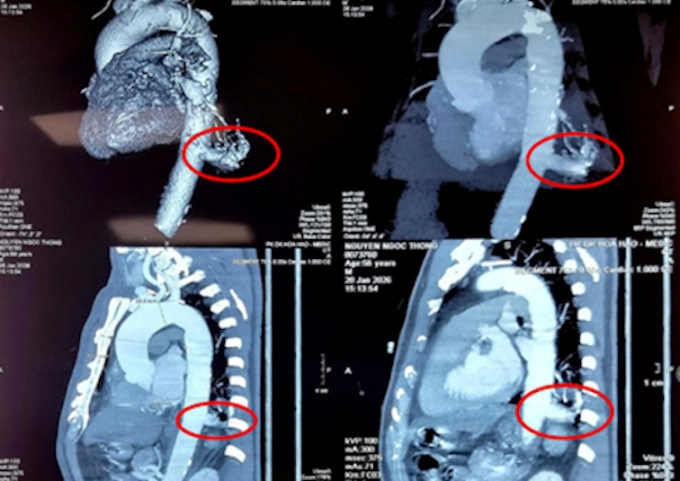

Bác sĩ xác định ở thùy dưới phổi trái của ông có một phần mô phổi phát triển bất thường (kích thước 23x26 mm). Khối mô này không có chức năng hô hấp, không thông với đường thở bình thường mà lại "ăn bám", nhận máu nuôi dưỡng trực tiếp từ động mạch chủ ngực xuống. Đáng chú ý, nhánh động mạch nuôi khối phổi thừa này có đường kính lên tới 17 mm - kích thước rất lớn và chực chờ vỡ bất cứ lúc nào.

Hình ảnh phần phổi dư thừa của bệnh nhân trên phim chụp. Ảnh: Bệnh viện cung cấp